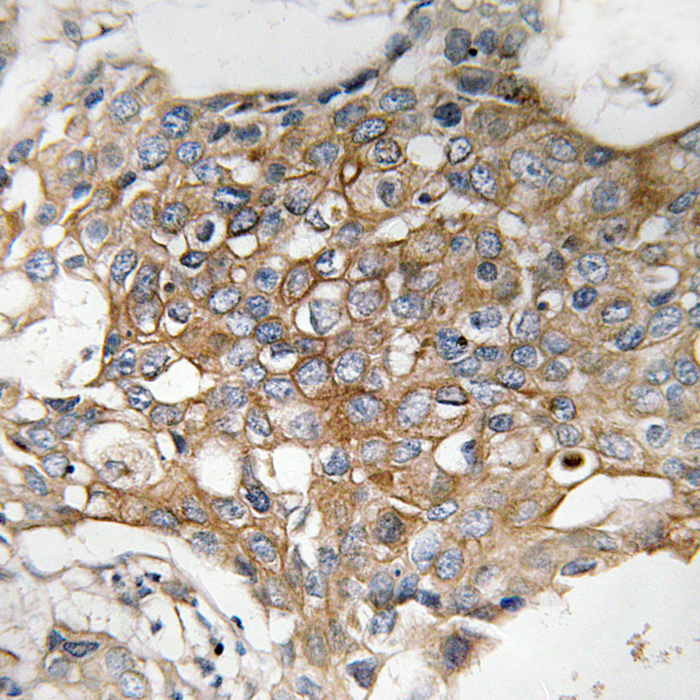

Immunohistochemical analysis of FAM11A staining in human breast carcinoma formalin fixed paraffin embedded tissue section. The section was then incubated with the antibody at room temperature and detected using an HRP conjugated compact polymer system. DAB was used as the chromogen. The section was then counterstained with haematoxylin and mounted with DPX.